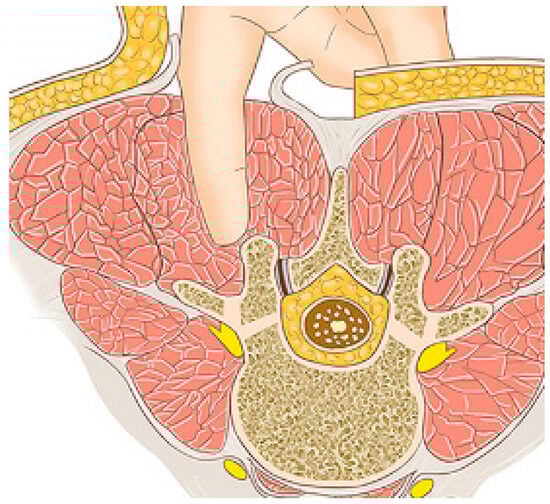

2.2. Surgical Technique